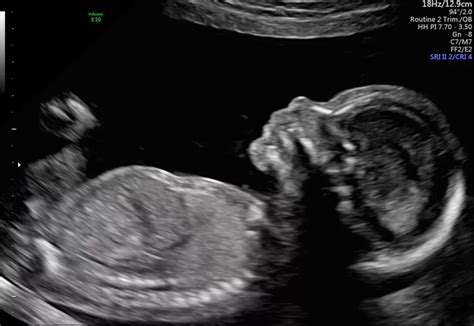

Alright, let’s get down to brass tacks: what exactly is this 20-week anatomy scan , and why is everyone talking about it? Simply put, it’s one of the most important ultrasound appointments you’ll have during your pregnancy, usually scheduled between 18 and 21 weeks . Think of it as a super detailed health check for your baby while they’re still snuggled safely inside you. The main purpose of this scan is to take a really thorough look at your baby’s development, checking everything from their tiny heart and brain to their fingers and toes. It’s truly incredible what modern technology can show us!

During the scan, a trained sonographer will methodically examine your baby, organ by organ, measuring various structures and assessing their growth. They’ll be looking for any signs of structural abnormalities or other conditions that might need further investigation. This isn’t just a casual glance; it’s a deep dive into fetal anatomy. They’ll check your baby’s brain, looking at its structure and development, and examine the spine to ensure the vertebrae are properly aligned and covered. The heart is a big focus, with the sonographer checking its four chambers, major blood vessels, and the rhythm of its beats – heart defects are among the more common findings that might require follow-up. They’ll also inspect the kidneys, bladder, stomach, and bowel to ensure they are present and functioning correctly. Your baby’s limbs, including arms, legs, hands, and feet, will be counted and checked for normal appearance. Plus, they’ll measure your baby’s head circumference, abdominal circumference, and femur length to assess their overall growth and ensure it’s on track for their gestational age. Beyond the baby, the sonographer will also assess the placenta’s position, the amount of amniotic fluid, and the umbilical cord, as these factors are crucial for your baby’s well-being and can sometimes be a source of unexpected findings .

So, why is this scan so important ? Well, guys, it’s all about early detection. Finding out about certain conditions early can allow healthcare providers to monitor the situation, plan for specialized care during birth, or even arrange for interventions after delivery. In some cases, knowing about a condition beforehand can help parents emotionally prepare and gather information and support. It’s also a fantastic opportunity for peace of mind – for the vast majority of parents, the scan confirms that their baby is developing perfectly, which is an incredibly reassuring experience . While the term “bad news” often comes up in online discussions, it’s more accurate to think of these as unexpected findings or anomalies that require further attention. The sonographer will be looking for specific markers for conditions such as spina bifida , major heart defects , cleft lip , and certain genetic syndromes. It’s a comprehensive check-up designed to give you and your medical team the best possible picture of your baby’s health. The 20-week scan is truly a pivotal moment in understanding and connecting with your developing child, offering insights that were unimaginable just a few decades ago. It’s a testament to medical advancements and a valuable tool for ensuring the healthiest possible outcome for both you and your little one. Don’t underestimate its importance, and try to view it as a proactive step in your pregnancy journey, not just a source of potential worry.